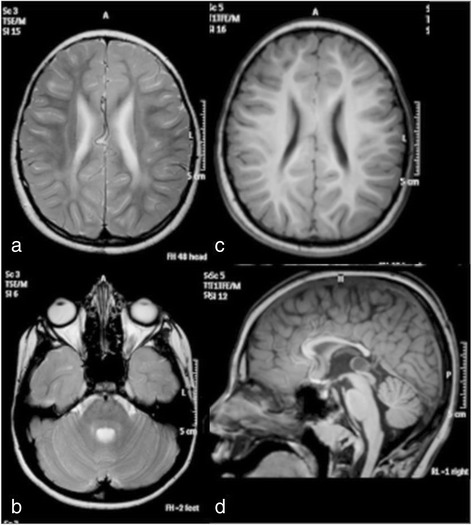

2020年12月,一个来自河北的男孩,在儿科遗传病专家会诊的建议下,来到佳学基因进行咨询。这个男孩是一对经过亲缘关系基因检测后确定没有血亲的父母所生的第一个孩子。除了母亲在怀孕第 7 个月期间描述说存在暂时性胎动减少外,怀孕期间平安无事。男婴孕37周后出生,出生体重2630克,身长49厘米,头围32厘米。 Apgar 评分为 10-10-10,围产期无并发症。由于双侧内斜视,这名男孩在 9 个月大时首次入院。然后他还被发现患有远视(+7-8)。定期眼科检查未发现其他变化。由于精神运动发育迟缓,他在 13 个月大时再次入院。他可以坐着,用他的整只手抓住并在它们之间移动,并用两个音节喋喋不休,对应于大约 6-7 个月的发育年龄。肌张力和腱反射正常。他在 3 岁左右学会了说几句话和独立行走。他的沟通能力在 5 岁时达到顶峰,当时他可以组合 2-3 个单词,而他的最佳运动功能是在 9 岁时,当时他可以在没有支撑的情况下上下坡。从那以后,他慢慢失去了发育技能,变得越来越僵硬。左旋多巴治疗试验没有效果。由于吞咽困难,他在 11 岁时接受了永久性胃造口术,尽管他仍然能够自己吃小块食物。在 16 岁的最后一次评估中,他是一个非常快乐和随和的年轻人,能够通过手势、声音、指点和大约 30 个手势和几句话进行交流。他能够在支持下行走约 100 米,并且具有相对良好的双侧钳抓精细运动功能。检查时,他的肌张力普遍增加,被认为是痉挛和强直的混合体,伴有大关节挛缩和右侧脊柱侧凸。肌腱反射通常随着左侧踝阵挛和右侧 Babinski 征而增强。没有不自主运动或共济失调迹象。他没有癫痫发作,脑电图也正常。头围和身高一直正常,没有其他器官受累的迹象。包括代谢筛查分析在内的常规实验室检查是正常的。在 8 岁时对大脑进行了 3 T MRI,显示出髓鞘形成不足和胼胝体变薄的轻度特征(图 1)。鉴于不寻常的表型,对 SLC17A5 功能的进一步分析表明是由尿液和成纤维细胞中游离唾液酸的升高驱动的。